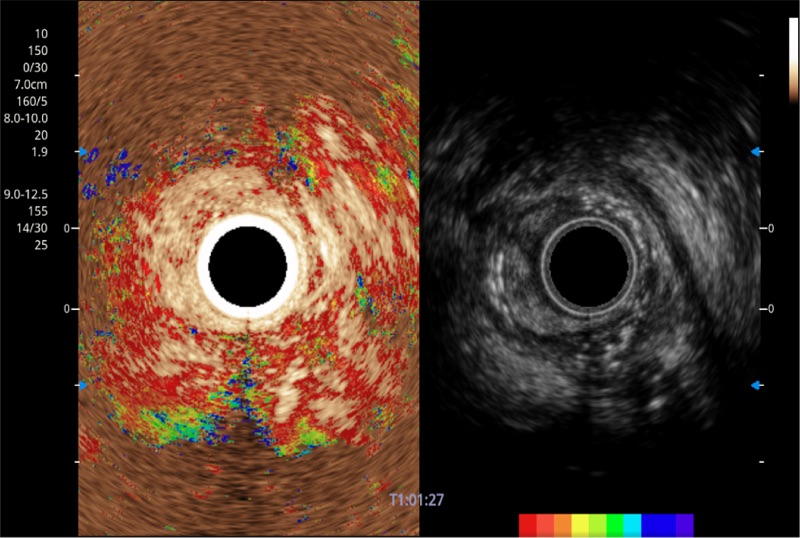

• 伪彩(Chroma)

可人为将灰阶图像转变成彩色的显示方式,增强人眼对于不同回声强度的敏感度,主观上增加了图像分辨率